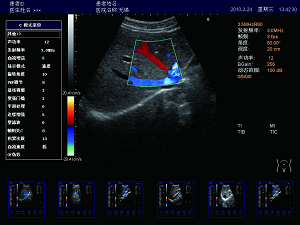

實時三同步

B型、彩色和頻譜多普勒三種模式同時實時顯示,獲

得更精確地采樣定位,更直觀進行對比分析。

肝臟 脾臟 多普勒血流

高效的多譜勒技術

多普勒幀相關 血流圖像更平滑更清晰。

多普勒快速優(yōu)化 對于危重病人,兒童可以在短時間內(nèi)獲得最佳的血流成像。

壁濾波器 增強血流邊緣清晰度,產(chǎn)生精準的發(fā)射波形,達到最佳匹配效果,提高全聲場的回波質(zhì)量。